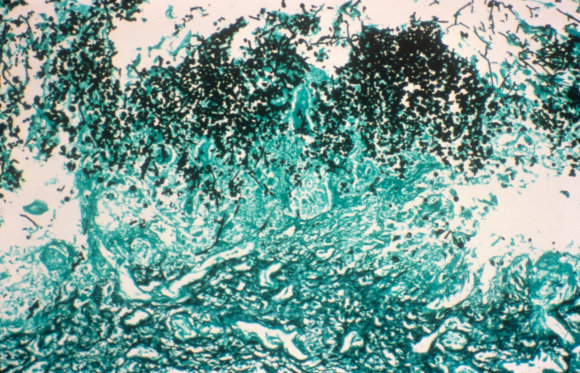

פטריות קשורות למספר מחלות והפרעות. צילום במיקרוסקופ אור של פטריות קנדידה בוושט | מקור: Science Photo Library

בדרך כלל אנו חיים בשלום עם הפטריות שלנו, אך חוקרים מצאו כי חלקן עלולות לצאת משליטה ולהפוך אלימות כשהמערכת החיסון נפגעת. דוגמה לכך היא הקנדידה, פטרייה נפוצה החיה במעיים ועל עורם של כ-70 אחוז מבני האדם. לרוב היא לא גורמת לתסמינים, אך כשמערכת החיסון נחלשת היא עלולה ליצור זיהומים בפה, במערכת המין ובמערכת העיכול.